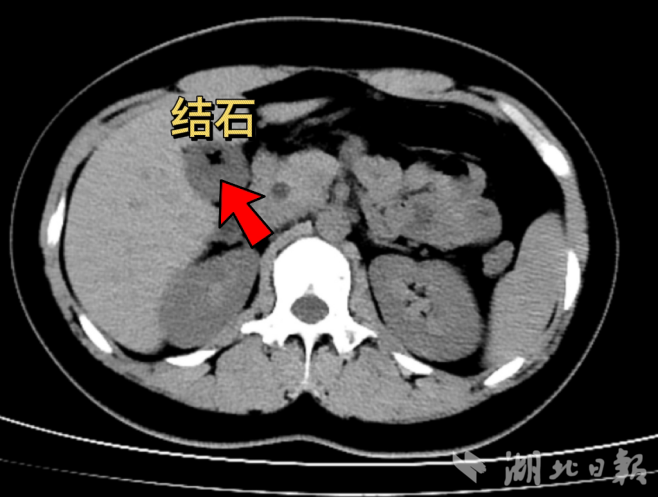

9月10日凌晨,国产亚洲精品久久久久久久_无码AV免费精品一区二区三区_99久久久无码国产精品免费人妻_精品人妻无码一区二区三区在线_无码专区久久综合久综合字幕_久久精品国产一区二区三区四区_真实一级一级一片免费视频_特级精品毛片免费观看_国产成人无码AA片免费看附属老年病医院普外科收治了一位18岁的胆囊结石女患者小袁。其家属介绍,因为常年不过早以及喜欢吃宵夜等生活习惯,小袁在一年前就查出患有胆囊多发结石,由于没有出现任何不适,她并没有在意。在当天晚上油腻饮食后,小袁开始出现剧烈的上腹部疼痛,随后前往医院就诊。

考虑到小袁年纪轻轻,其家属也强烈希望保留胆囊。李纯坚经过系统检查,并结合术前检查提示的胆囊收缩功能以及优化胆汁的功能还存在,确认小袁的胆囊功能尚好,符合保胆取石术的条件,于是果断选择给患者施行保胆取石术。在腹腔镜和胆道镜微创技术下,成功取出了胆囊内六枚板栗大小结石。整个手术过程顺利,小袁术后恢复迅速,次日便能下床活动,疗养几日后便康复回归正常生活。